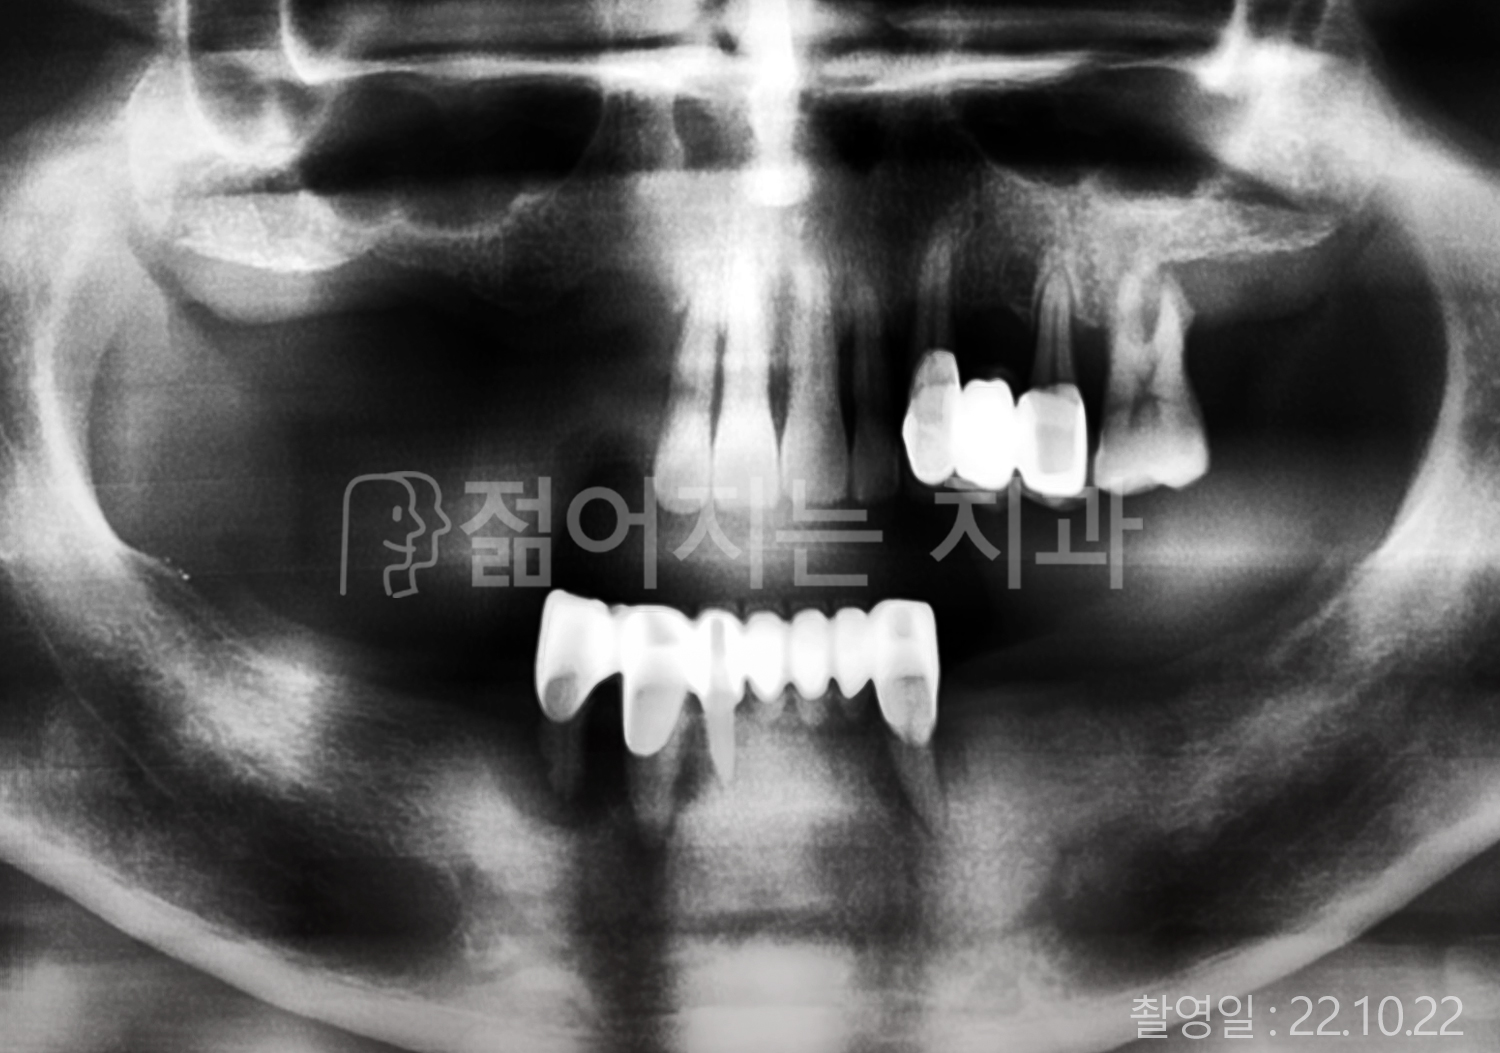

• 50대 전체치아 10개 이상 임플란트

• 50대 고혈압, 고지혈증 전체치아 10개 이상 임플란트